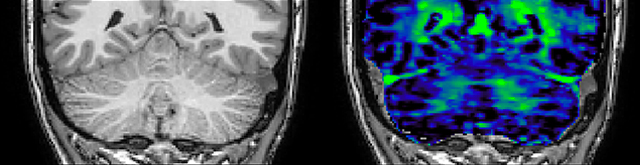

QSM based on a Compressed SENSE multi-echo SWI.

Dr. Rauscher says, “With better gradients we can use a shorter echo spacing on the spin echo, so we get better sampling of the rapidly decaying myelin signal, which typically has T2 of around 10-20 milliseconds at 3 Tesla. If we can reduce echo spacing from about 8 to 5-6 milliseconds, we get a much better sampling of the short decay component and increase our SNR, which is a big advantage. The same is true for multi-echo gradient echo which we use for susceptibility mapping and for mapping venous vessels in MS.”

He says the accelerated scanning is achieved via the use of Compressed SENSE and MultiBand SENSE. “We can use Compressed SENSE acceleration factors of about 10 on a 3D FLAIR for instance, which is quite remarkable compared with what we saw with the Achieva. With 3D FLAIR, we can push the spatial resolution to 0.3 cubic mm and it works. Previously, our 3D FLAIR scans lasted about 8 minutes, but now with Elition they are five minutes. The SNR is also visibly better. Our SWI and QSM scans look fantastic. Also, since a lot of neuroimaging is EPI based, using the MultiBand SENSE technique can increase temporal resolution and make it possible to run complicated DTI scans relatively quickly.”